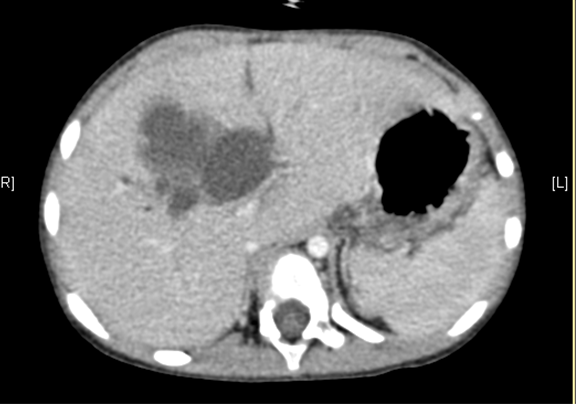

术前CT检查:

静脉期

平衡期

腹部CT 增强:1. 肝内外胆管扩张,考虑胆总管囊肿并胆系扩张可能性大2. 胆囊结石。